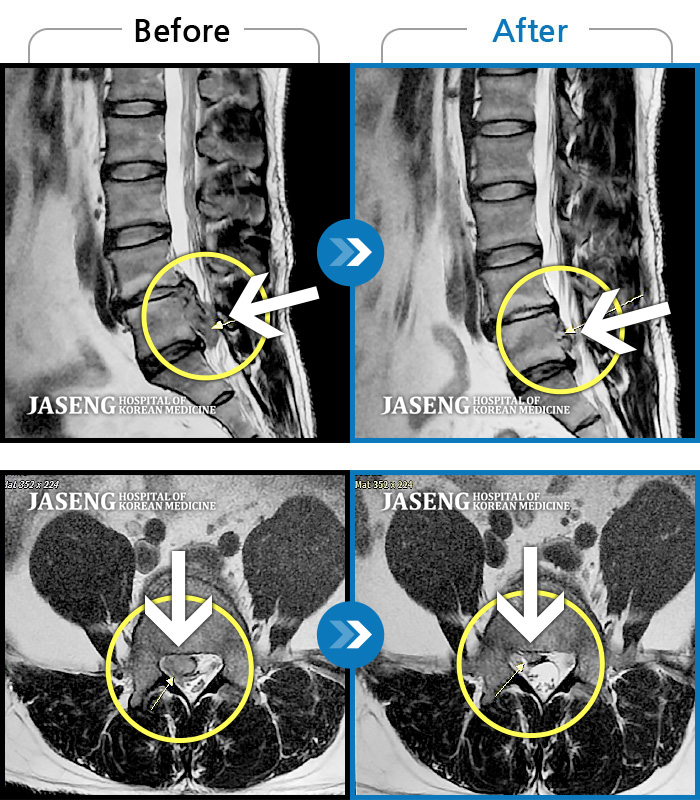

Before

After

환자에게 사전 동의를 받아 동일 조건에서 촬영되었습니다.

개인에 따라 치료 후 부작용이 발생할 수 있으니 의료진과 상담 후 치료를 진행하시기 바랍니다.

우측 엉치부터 우측 다리부터 발끝까지 저리고 아프다. 감각까지 먹먹하다.

양측 허리부터 양측 골반 통증, 보행 시 다리를 끄는 증상